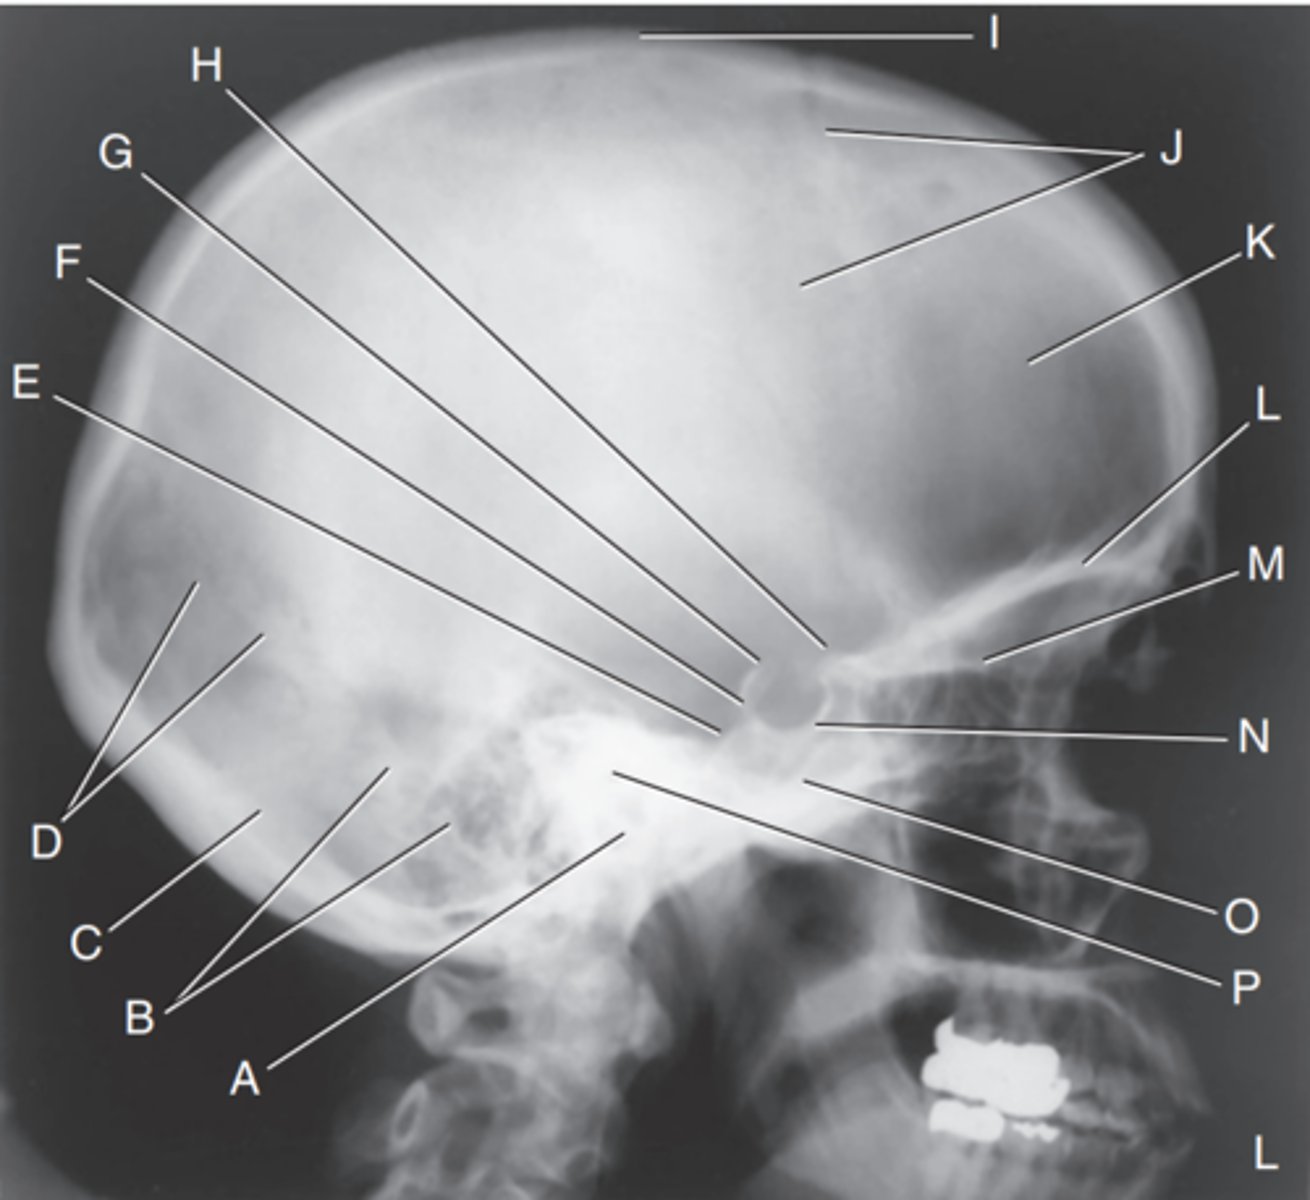

EAM

Label A

Mastoid portion of temporal bone

Label B

Occipital bone

Label C

Lambdoidal suture

Label D

Clivus

Label E

Dorsum sellae

Label F

Posterior clinoid processes

Label G

Anterior clinoid processes

Label H

Vertex of cranium

Label I

Coronal suture

Label J

Frontal bone

Label K

Orbital plates

label L

Cribriform plate

Label M

Sella turcica

Label N

Body of sphenoid (sphenoid sinus)

Label O

Petrous portion of temporal bone

Label P